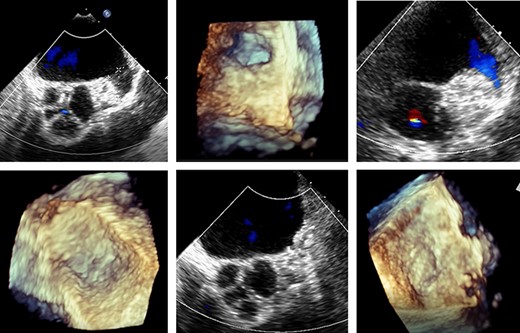

A cardiac computed tomography excluded coronary heart disease and showed the LAA was raised anteriorly at the level of the left upper pulmonary vein and had a chicken-wing shape, with an anterior curvature to the right (Fig. 3). Ectasia of the ascending aorta (41 × 41 mm at pulmonary artery level) was detected.

Preoperative cardiac computed tomography (CT) ‘Chicken wing’ morphology of the LAA; cardio CT for presentation of the special (Chicken wing morphology) of the LAA and for exclusion of coronary heart disease before surgical LAA clip implantation.